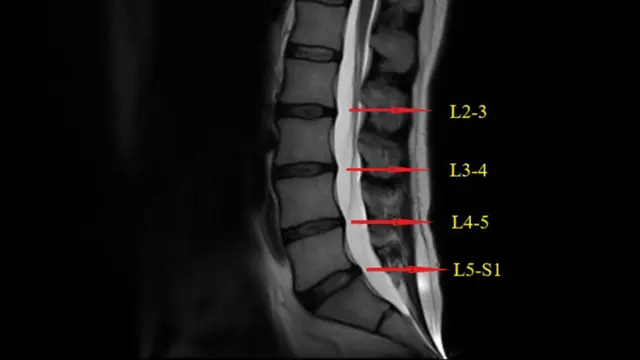

मुंबईतल्या सैफी हॉस्पिटलमधील ऑर्थोपेडिक डॉक्टर अबी तुराब चुनिया यांच्या मते, सामान्यतः आढळणाऱ्या पाठदुखीसाठी शस्त्रक्रियेची गरज नसते. परंतु, काहीवेळा 'स्लिप डिस्क' (slipped disc) सारख्या गंभीर कारणामुळेही कंबरदुखी होऊ शकते. यामध्ये, नसेवर तीव्र दाब आल्यास शस्त्रक्रियेची गरज भासू शकते, जी नसेवरील दाबाच्या तीव्रतेवर अवलंबून असते. त्यामुळे, कंबरदुखीची अनेक कारणे असू शकतात.

दुसरीकडे, पाठीच्या मणक्यात काय प्रॉब्लेम आहे, हेच कळणं अवघड जाते. कोणती नस किंवा स्नायू दाबलाय हे Xray, MRI Scanने सहज शोधणं शक्य होत नाही. त्यामुळे हॉस्पिटलमध्ये सामान्य लोकांचे खूप पैसे जातात.

मणक्याला फ्रॅक्चर झालं असेल, मणक्यात कॅन्सरची गाठ असेल किंवा तिथे जखम झाली असेल तरच कंबरदुखीचं कारण स्पष्टपणे समजू शकतं, असं हॅनकॉक सांगतात.